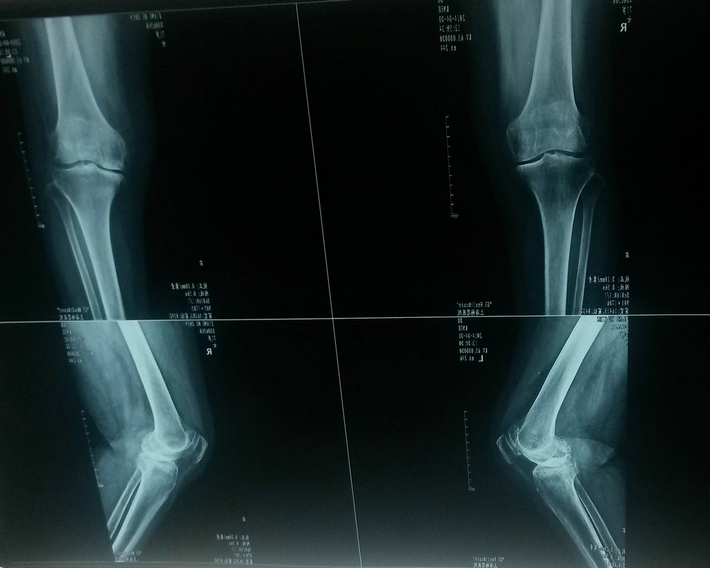

内侧半月板损伤

膝关节支撑着人体重量的80%,当负重额外增加(如挑担、搬运、提重物等),或偶尔病毒侵入膝关节周围的肌束、滑膜等组织,引起相应周围的软组织,腘部血管、韧带等产生无菌性炎症疼痛或局部水肿。随着年龄的增长,内分泌功能变化,膝关节腔受到支撑力影响而发生变化。原先的膝关节正常支撑点,逐渐形成了新的错位支撑力点。此也多半由于胫腓韧带积累性的劳损,最先发生变化,引起支撑点外向侧飘移,促使膝关节腔内结构组织的痉挛,形成内侧半月板磨损或率先发生半月板破损,使膝关节骨性结构变得越来越狭窄。腘部的腘肌与静脉相应受到影响,最终发生了功能障碍和疼痛。伴随着就会出现股骨头、膝关节、踝关节形成病态角度。因而也会导致髋关节、踝关节的力点飘移,也产生相应的疼痛。